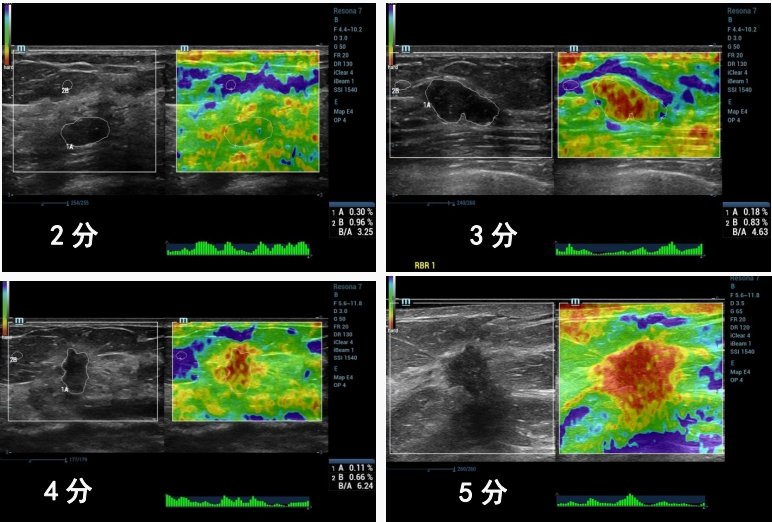

超声应变式弹性成像5分法的图示